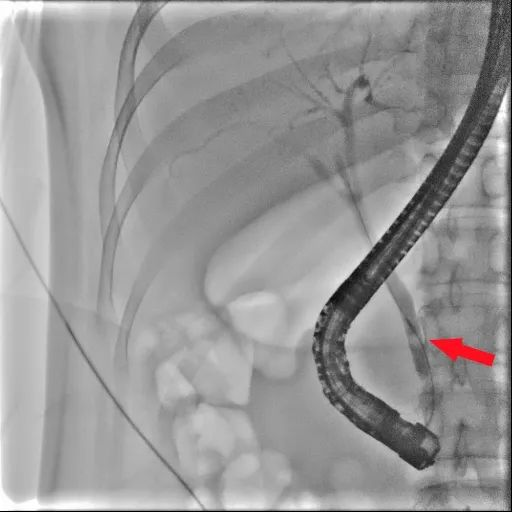

患者为年轻女性,反复腹痛3天入院,腹部CT显示:胆总管下段结石、肝内外胆管轻度扩张;肝功能多项指标明显升高。经保守治疗后,患者腹痛症状仍反复。李捷壮主任医师、刘烈辉副主任医师带领的ERCP团队对患者做了详细的体格检查、仔细判读相关辅助的检查,明确诊断:胆总管下段结石伴胆管炎。经过全面的术前讨论及科室团队反复商酌,决定为患者实施“经内镜逆行胰胆管造影+胆总管结石取出术”治疗。

▲X线下结石

患者术程顺利,术后患者安返病房,患者自诉无腹痛等不适,术后2天复查肝功能较前明显好转,术后3天患者无特殊不适,予出院。